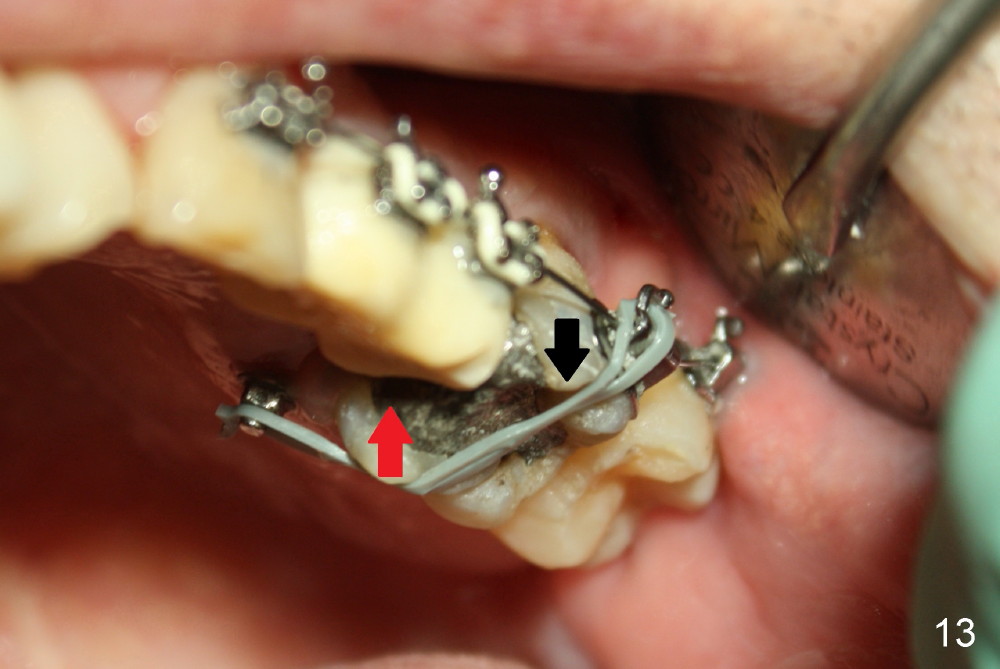

A 51-year-old man needs implants at the sites of #12,13,19 (Fig.1). The teeth #12 and 13 are extracted. An implant is placed at #19 (Fig.2 <). After osteointegration, an abutment is placed (Fig.2 A). The opposing tooth, #14, is found supraerupted. Two mini-implants are placed at the mesiobuccal and distolingual areas of #14 (Fig.3 (mirror view) <) and a power chain (*) is placed for intrusion. In the next 8 months, these 2 mini-implants become loose. Two new mini-implants are placed in the mesiolingual and distobuccal regions (Fig.4 ^). The one in the distobuccal region is loose after a while (Fig.6,7 >). In brief, mini-implants are not efficient in intrusion. At this time, the implants at the sites of #12,13 apparently osteointegrate (3 months post placement) and abutments are placed (Fig.4). Provisional crowns are fabricated (Fig.5). Brackets are placed between #11 and 15 with the bracket at #14 placed more coronally than those of the neighboring teeth (Fig.6-8). Mesially there are two excellent anchorages (#12,13) as well as the mesiolingual mini-implant. The distal anchorage is #15. In the next 5.5 months, the tooth #14 is intruded (Fig.9,10), but the 2nd molar is mobile (not as strong as #14). A longer mini-implant is placed in the distobuccal corner (>, more apical than before (Fig.7)). The distobuccal mini-implant is found to be mobile in 3 weeks (Fig.11). It appears that there is enough clearance for restoration of #19 (Fig.12). Power chains are placed between the mesiolingual mini-implant and #14 buccal tube until the appointment for crown prep. In this way, the lingual cusps may ascend (Fig.13 red arrow), while the buccal ones may descend (black arrow). The occlusal clearance will be more favorable.